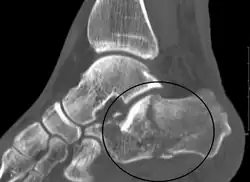

La radiographie standard est l'examen de première intention utilisé lorsqu'une fracture du calcanéus est suspectée. Les incidences recommandées sont : face, profil, dorsiflexion et rotation interne. Cependant, la visualisation de l'anatomie calcanéenne est limitée, notamment au niveau du ligament talo-calcanéen. Le scanner est actuellement la modalité d'imagerie de référence pour l'évaluation des lésions calcanéennes et a remplacé la radiographie standard dans la classification des fractures du calcanéus[11]. Les coupes axiales et frontales sont utilisées pour une bonne visualisation des ligaments de la base du pied.